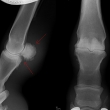

Těžká artróza ve spěnkovém kloubu

Podotrochleóza